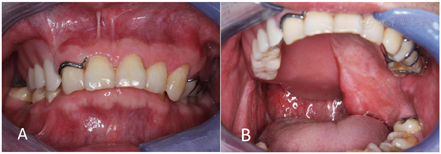

颌面部基本对称,开口约2横指,口内26、27、36、37缺失,缺牙区牙槽骨缺失,左侧软腭完全缺失伴小部分硬腭缺失。左颊、左咽侧壁见皮瓣修复,有瘢痕挛缩。12~21固定桥修复。构音不清,饮水时见鼻漏(图1)。病理结果提示:(癌灶)形态学结合原病史,符合高-中分化鳞癌,浸润肌层。